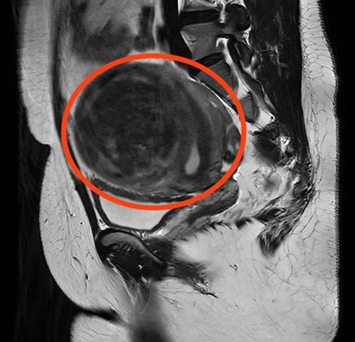

“2年前,肌瘤开始明显增大,今年频繁出现尿频、尿急症状,严重影响了日常生活。”曹女士介绍,为寻求进一步治疗,她来到香港马会app 妇科门诊就诊。经过B超检查显示,曹女士子宫左侧壁肌瘤内可见102*88*92mm的包块,考虑为子宫肌瘤。面对如此“巨大”的肌瘤,曹女士忧心忡忡,以为只有通过开腹手术才能将其切除,手术过程及术后遗留的疤痕让她既害怕又焦虑。

CT检查显示子宫左侧壁巨大肌瘤

6月3日,在完善相关术前准备后,妇产科三区魏馨主任带领团队为曹女士实施了全麻下单孔腹腔镜子宫肌瘤剥除术。手术过程中,手术人员凭借精湛的技术,通过腔镜下视野,用“削苹果式”逐步减容技术,如同削苹果皮般将瘤组织分离成一条长达2.4米的条索,然后通过腹部2-3公分的切口将肌瘤成功取出。术后,在妇产科医护团队的精心护理下,曹女士恢复良好,5天后康复出院。

经单孔腹腔镜,巨大子宫肌瘤被分离成2.4M长的条索